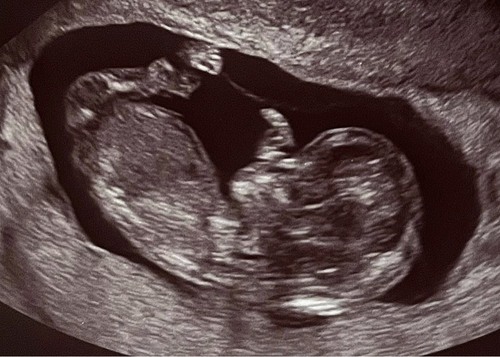

Das ist mein Ultraschallbild aus der 21SSW beim Organscreening. Er wiegt ca 400 gramm und ist 24 cm groß.